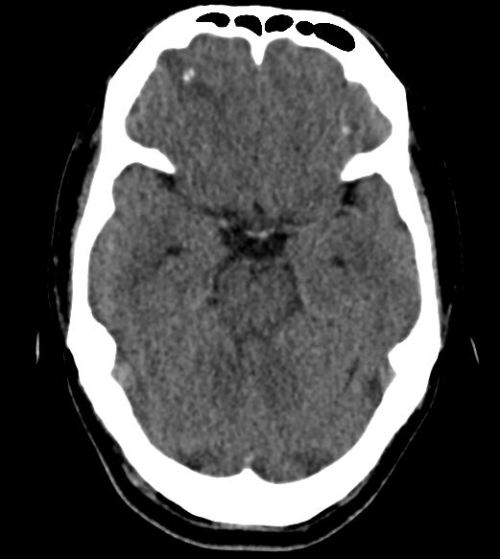

A young Indian national presented with his first ever episode of generalized tonic-clonic seizures and was hospitalized. He was previously healthy, vegetarian, and had been based in Singapore for the past 3 years, working in the construction industry. A plain CT head performed at the emergency department showed a spot of calcification at the right […]